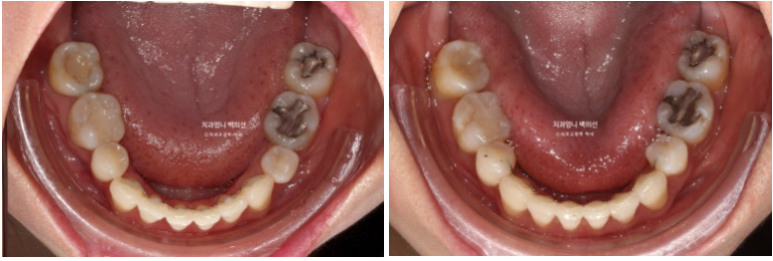

23.08~25.06

소량의 치간삭제로 기존의 블랙트라이앵글 사이즈를 줄였습니다.

2급이었던 양측 어금니 교합관계는 비로소 1급이 되었습니다.

이제 앞니 중심선은 코와 인중과 정확히 맞습니다.